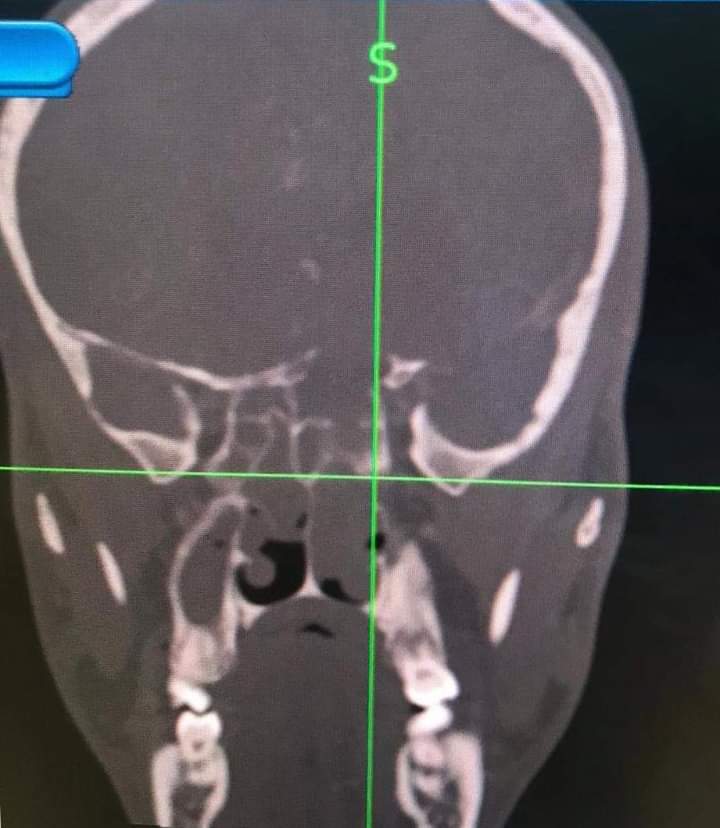

قام فريق طبي من دائرة الأذنية في الخدمات الطبية الملكية برئاسة العقيد الطبيب نبيل الشواقفة مستشار جراحة الأنف وقاع الجمجمة بإجراء عملية تنظير معقدة ونادرة لشاب يبلغ من العمر ٢٠ عاما، يعاني من التهاب فطري حاد ممتد إلى قاع الدماغ وحجرة العين مع وجود ثقب في قاع الجمجمة.

وبين الشواقفة ان المريض عندما راجع عيادة الأنف والأذن والحنجرة في مدينة الحسين الطبية كان يشكو من صداع شديد وانسداد في الأنف وصعوبة في التنفس، وبعد إجراء الفحص السريري والشعاعي تبين وجود إلتهاب حاد ممتد إلى قاع الجمجمة وحجرة العين وثقب في قاع الجمجمة، تقرر على أثرها إجراء العملية التي تعتبر من العمليات النادرة والمعقدة التي تحتاج فريق طبي متخصص .